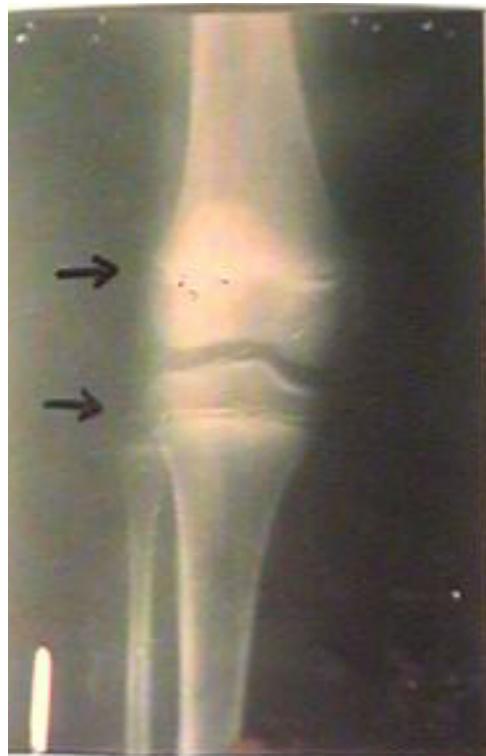

- Knee Joint (Below 21 years):

- Lower end of femur not united with shaft

- Upper ends of tibia and fibula not united with shafts